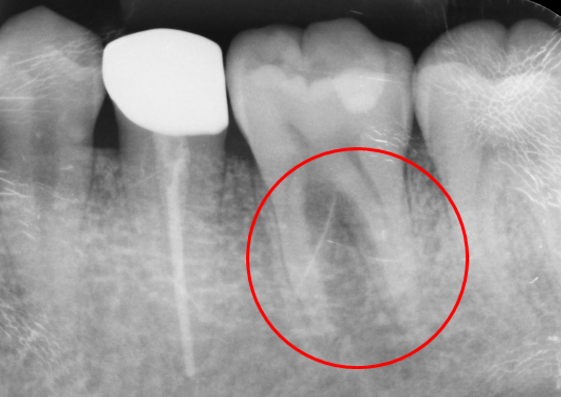

CASE03

歯根端切除術逆根管充填50代 女性

初診時

-

治療後

1年後

主訴

前歯の歯ぐきが腫れた。

治療の概要

根管治療では治らない歯に対して、根の先端を切除しそこから特殊な器具で穴をあけ、MTAという材料を充填し封鎖をはかりました。

1年後のレントゲンでは、根尖の病変がなくなり、骨ができています。

リスクと副作用

コストがかかる。 外科処置が必要になる。

- 治療費

- 121,000円

- 治療回数

- 1回